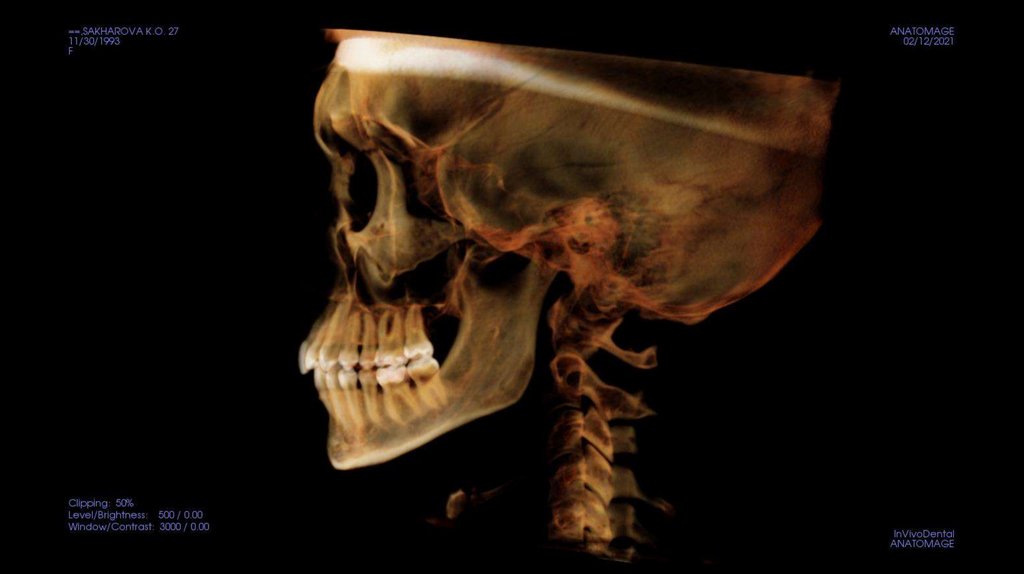

По рассчетам снимков:

• Ретрузия резцов верхней челюсти

• Компрессия головок суставов, особенно правого( началось

ремоделирование)

• Костная ассиметрия(10 мм)

• 2 класс

• 25, 46 зуб – нуждается в санации

• Требуется профессиональняа гигиена полости рта

• Клиновидные дефекты 43, 44

• 18, 28, 38, 48 отсутствуют.

Скелетный: II класс.